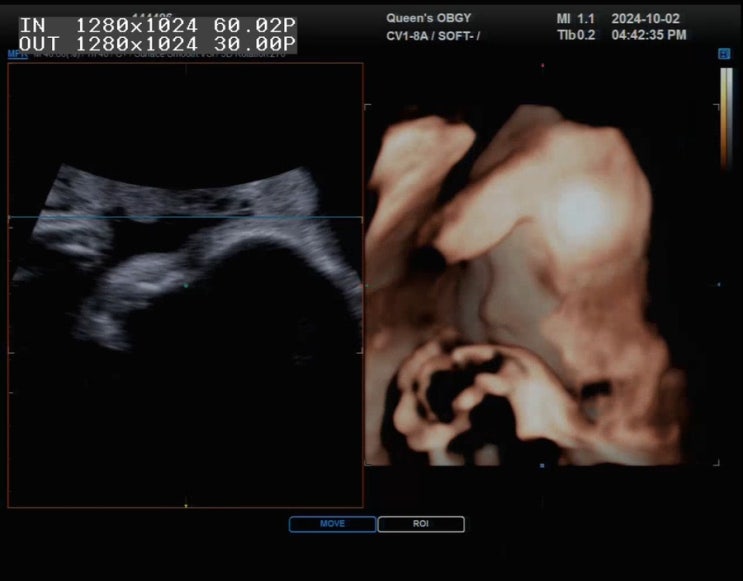

[임신기록] 30주 입체초음파

으아니? 벌써 30주라니 믿을 수 업쒀 !! 그치만 신나? 고대하던 입체초음파 예약날인데다가 오랜만에 친...